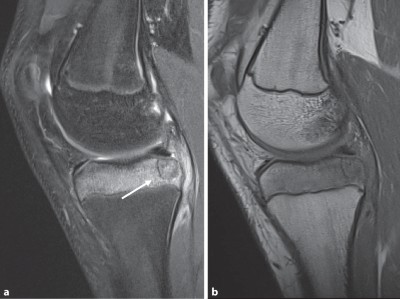

Schmerzbedingt kann ein 15-Jähriger sein rechtes Knie nur eingeschränkt bewegen. Seit etwa 3 Monaten verschlechtert sich die Symptomatik, insbesondere beim Sport. ASS bringt keine Besserung. Welche Diagnose stellen Sie? Zur Wahl stehen eosinophiles Granulom, Riesenzelltumor, Chondroblastom, Osteoidosteom, Osteomyelitis.

Warum schmerzt das Knie des 15-Jährigen?

Chondroblastom in der MRT/© Camp L et al. / all rights reserved Springer Medizin Verlag GmbH, Patellafraktur/© K. Fehske · R. Hoffmann / all rights reserved Springer Medizin Verlag GmbH, Röntgenaufnahme eines nicht ossifizierenden Fibroms /© Weber M et al. / all rights reserved Springer Medizin Verlag GmbH, Cholesterolgranulom im MRT/© Frederik F/ all rights reserved Springer Medizin Verlag GmbH, pathologische distale Femurfraktur/© Omar M et al. / all rights reserved Springer Medizin Verlag GmbH, Frau unkenntlich fasst sich ans Knie/© Pornpak Khunatorn / Getty Images / iStock (Symbolbild mit Fotomodell), Echondrom/© Springer Medizin, Ausprägungen einer antiresorptivaassoziierten Kiefernekrose (AR-ONJ)/© Ristow, O. et al. / all rights reserved Springer Medizin Verlag GmbH, Stereotaktische Strahlentherapie (SBRT) einer solitären ossären Metastase in dem Brustwirbelkörper/© Springer Medizin Verlag GmbH, Arzt oder Pfleger schaut auf eine im MRT Eingang liegende Person/© [M] oksanazahray / stock.adobe.com (Symbolbild mit Fotomodell), Wirbelsäulenmetastase/© stockdevil / stock.adobe.com, Bluttransfusion/© Tobilander / Fotolia, Ärztin und kleines Mädchen mit Kopftuch/© FatCamera / Getty Images / iStock (Symbolbild mit Fotomodellen), Inhalt eines Fläschchens wird aufgezogen/© MarianVejcik / Getty Images / iStock, aneurysmatische Knochenzyste im Bereich des rechten distalen Femurs/© Springer Nature / all rights reserved Springer Medizin Verlag GmbH, Ewing-Sarkom/© Botos B. Z. et al. / all rights reserved Springer Medizin Verlag GmbH, Tumorkalzinose in der Hüfte/© Sukun A & Weber M.-A. , Computertomografie-gesteuerte periradikuläre Therapie auf Höhe von Lendenwirbelkörper 5/Sakralwirbelkörper 1 rechts/© Institut für Diagnostische und Interventionelle Radiologie des Klinikums St. Marien Amberg, Körperstereotaxie einer Lebermetastase im Segment VIII am MR-LINAC/© Ehret, F. et al. / all rights reserved Springer Medizin Verlag GmbH, Search Icon, Arthropedia, Ärzteteam führt Hüftoperation durch/© ATRPhoto / stock.adobe.com (Symbolbild mit Fotomodell), Gebrochener Fuß im Gips/© Aleksandr Kirillov / stock.adobe.com (Symbolbild mit Fotomodell)